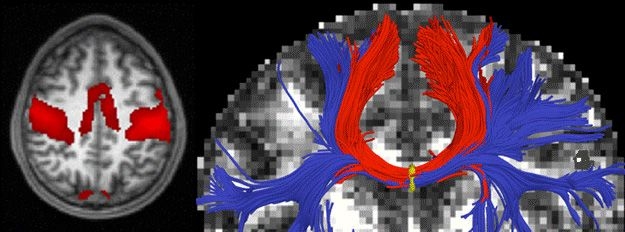

Left: A functional magnetic resonance imaging (MRI) scan with cortical regions strongly correlated with motor activity highlighted in red. Right: A diffusion MRI scan with white-matter bundles passing through the corpus callosum shown in blue and red.

Images: Marek Kubicki, Brigham and Womens' Hospital, Harvard Medical School

The algorithm, developed by Polina Golland, an associate professor of computer science, and graduate student Archana Venkataraman, extracts information from two different types of magnetic resonance imaging (MRI) scans. The first, called diffusion MRI, looks at how water diffuses along the white-matter fibers in the brain, providing insight into how closely different areas are connected to one another. The second, known as functional MRI, probes how different parts of the brain activate when they perform particular tasks, and so can reveal when two areas are active at the same time and are therefore connected.